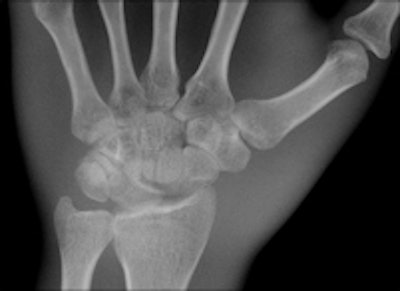

Two images of a hand phantom obtained using different equipment: Fuji's CR system and DRX-1 from Carestream. All images courtesy of Dr. Thomas Lehnert.

A third image of a hand phantom obtained using DR9500 from Carestream.Identical in size to a standard CR cassette, the detector can be inserted into an existing wall stand or table Bucky and used in combination with existing x-ray generators from a number of original equipment manufacturers, presenting an attractive option for modest-budget facilities. The flexibility of the portable detector provides great advantages in time-critical environments where an x-ray image can now be captured and viewed in less than six seconds, he explained.